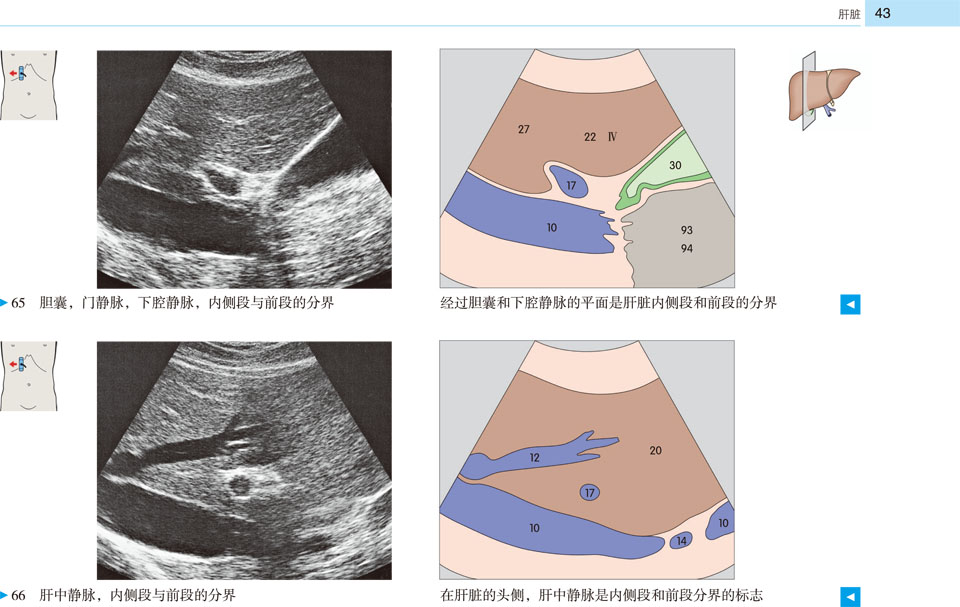

本书提供了全新的、高质量的超声图像和示意图,标示清晰、色彩丰富,为初学者带来极大的帮助。展示了腹部、盆部、甲状腺超声的所有标准切面和扫描路径,标示了各解剖结构和间隙在三维空间的解剖细节及其与超声的关系;并展示了探头定位,以及生成的截面图像、解剖结构、扫描平面在器官中的位置。本书作为优秀的初学者向导,适用于医学生、超声科医师、临床各科医师。